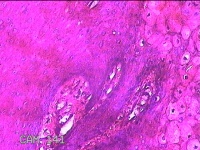

下唇肿物

性别

男

年龄

22岁

临床诊断

口腔黏液腺囊肿

下唇肿物一个月余。

大体所见

图4